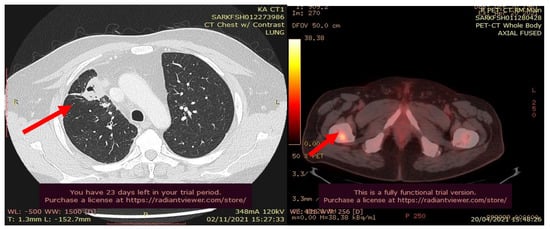

In July 2021, a 60-year-old patient came to our Cryosurgery unit, provided with a CT scan of the chest dated April 2021. The CT scan revealed the presence of a hyper-metabolic lesion with a size of 2.8 cm and involving the right upper/middle lobe related to the neoplastic process. The presence of hypermetabolic lytic bone lesions involving the right proximal femur T-10 and the left transverse process of T-9 was also confirmed, highlighting bone metastasis (Figure 4).

The process for patients with metastatic disease should include abdominal and pelvic CT scans. This is the reason why an abdominopelvic CT scan with contrast was performed in July 2021. There was no evidence of abdominopelvic metastases but always manifestations of diffusion of bone metastases. A specular nodule was noted in the right upper lobe with evidence of bilateral pulmonary nodules, and pleural and bone metastases. The pleural biopsy performed confirmed the presence of metastatic adenocarcinoma.

Figure 4. CT scan (left) and Pet- CT (right) images from April 2021 with evidence of bone metastases. The arrows indicate the tumor’s location.